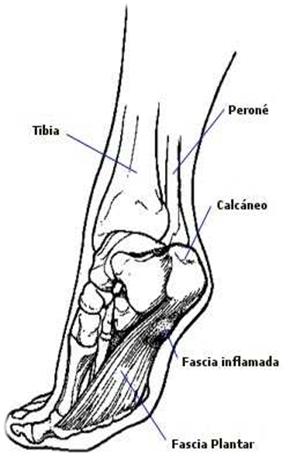

Fascitis plantar

¿Qué es la fascia plantar?

La fascia plantar o el ligamento del arco del pie es una banda que discurre desde debajo del talón en dirección a los dedos.

Cuando la fascia se estira o se usa demasiado (deportistas), puede resultar inflamada. Cuando esto sucede, puede ser dolorosa y hacer más difícil el caminar.

¿Cuales son los síntomas de la fascitis plantar?

• Dolor e hipersensibilidad localizados a lo largo de la fascia plantar.

• La aparición de un nódulo o un bulto del tamaño de un garbanzo en la fascia plantar que puede indicar su rotura parcial.

¿Qué puede hacer el deportista para prevenir la fascitis plantar?

• Reposo (usando muletas para descargar el pie si es necesario).

• Masaje de la zona con hielo.

• Estiramientos de la fascia plantar y del tendón de Aquiles y gemelos.

• Acudir al podólogo para el tratamiento y el uso de una plantilla de descarga a medida.